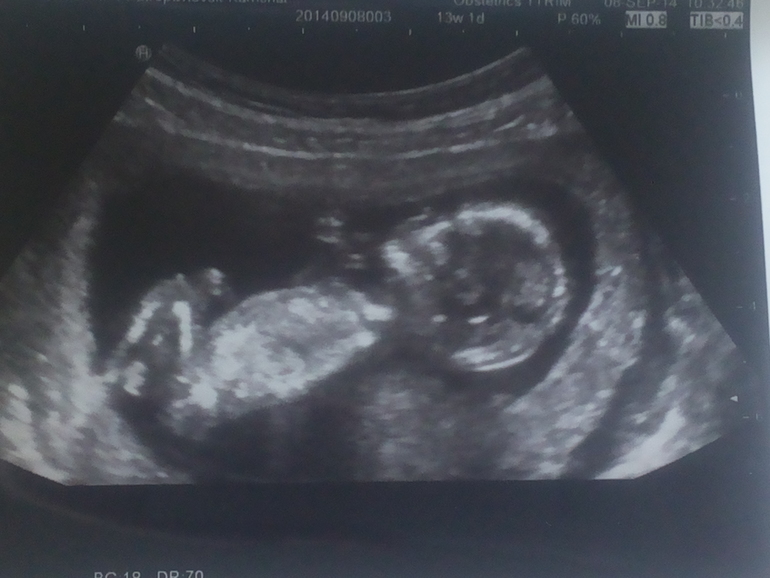

Наш первый скрининг!

Ну вот и я отчитываюсь))) Срок 13 нед. и 1 день. У нас все хорошо, КТР 74 мм, ЧСС 156, ТВП 1.7, кости носа 2.8, плацента по задней стенке, опережаем срок на 6 дней(по всем замерам на 13.6) и ......у нас мальчик!))) ) Желудок был у него полный, видимо только пожрамши ))) Правда был небольшой тонус из-за нервов (врач сказала не кушать перед скринингом, а меня ОЧЕНЬ тошнит на голодный желудок и самочувствие совсем хреноватое, аж трясет. Но на узи оказалось что кушать можно было, врача при встрече прибью). Малыш посасывал пальчики и лежал нога на ногу (как мужики когда развалятся))) Моя отслойка исчезла, чему я безмерно рада! (Теперь буду насиловать мужа т.к. из-за отслойки нельзя было шалить

Мой малыш, мое солнышко, моя радость